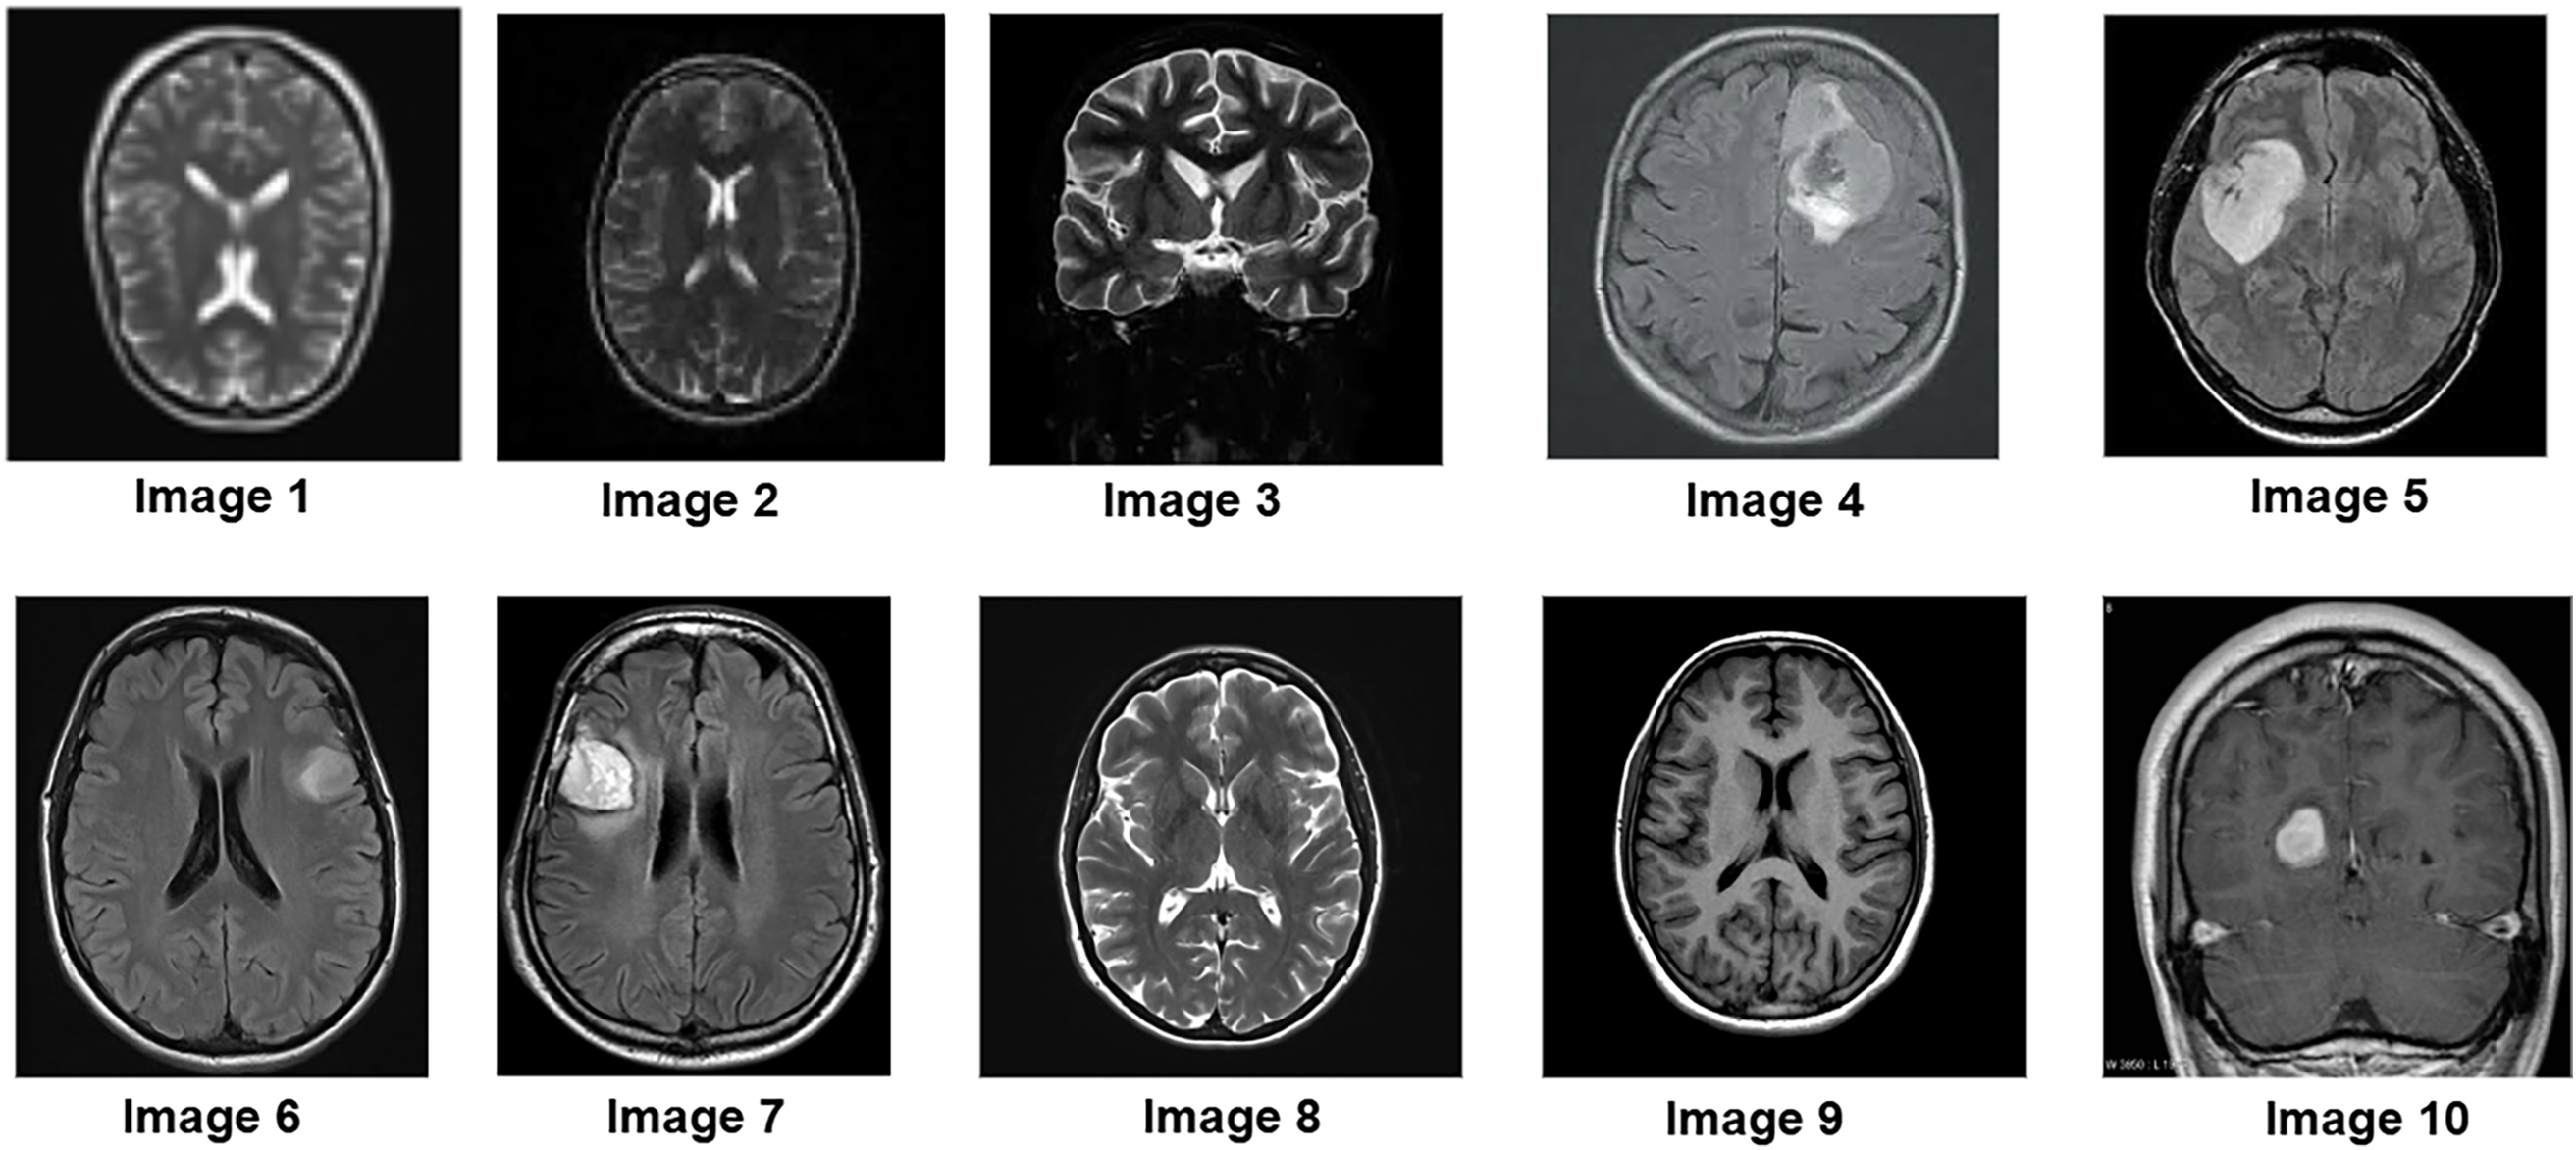

To further assess the algorithm’s performance, experiments were conducted on a clinical MRI dataset from Kaggle, which includes a variety of tumor patterns with different intensity distributions. The segmentation performance of the P-GWO-FCM method was compared to that of FCM and sequential GWO-FCM. The effectiveness of these three methods was evaluated using the DBI, PEI and PCI metrics, with the results presented in Table 4. Fig. 5 showcases a selection of MRI images from the clinical dataset used in the experiments, displaying 10 images of varying sizes to demonstrate the robustness of the proposed approach. These images were segmented using all three algorithms. Fig. 6 illustrates the segmentation results obtained for these 10 brain MRI images using the P-GWO-FCM method.

Figure 5: Samples of brain MR images from clinical dataset